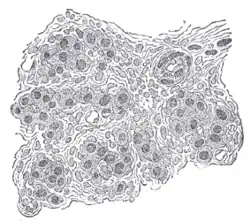

Section of part of human carotid body. Highly magnified. Numerous blood vessels are seen in section among the cells. | |